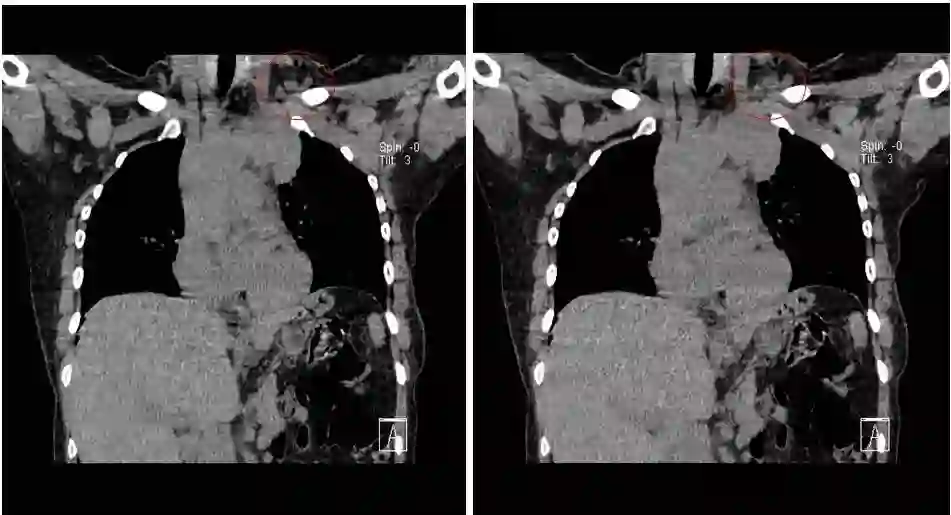

接受TC(卡铂)+曲妥珠单抗单周方案治疗。治疗2个周期后复查:淋巴结彩超示:左锁骨上淋巴结缩小,大的0.6×0.4cm;复查胸部CT示:左侧纵隔肿物缩小,最大截面约6.0×2.9cm。治疗4个周期后再次复查,淋巴结彩超示:左锁骨上淋巴结缩小,大的0.6×0.4cm;复查胸部CT示:左侧纵隔肿物缩小,最大截面约3.1×2.4cm。治疗6个周期后再次复查,淋巴结彩超示:左锁骨上淋巴结缩小,大的0.3×0.3cm;复查胸部CT示:纵膈肿物缩小明显,病灶局部包绕头臂静脉,与胸壁边界不清。评价治疗有效,继续行TC(卡铂)方案化疗+靶向治疗。治疗8周期后再次胸部CT示:纵隔肿瘤缩小明显,最大截面由最初的7.2×2.9cm缩小为2.7×2.9cm,评价为PR。8周期治疗后,患者出现腹泻,大便次数8-10次/天,水样便,影响日常生活,根据NCI分级属3级重度腹泻。10天左右缓解;II度骨髓抑制。患者拒绝继续化疗,曲妥珠单抗改为21天/周期。

图6. 治疗过程中胸部CT病灶变化